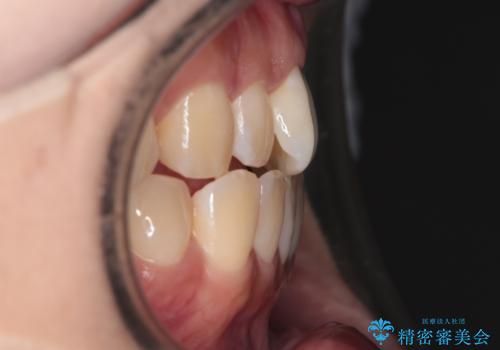

【インビザライン】前歯の捻れ気になる

- 上の前歯の捻れを主訴に来院されました。

前歯の捻れとがたつきを改善するために、IPR(歯と歯の間を削る処置)と歯列拡大をすることで歯並びを整えていく治療計画を立てました。